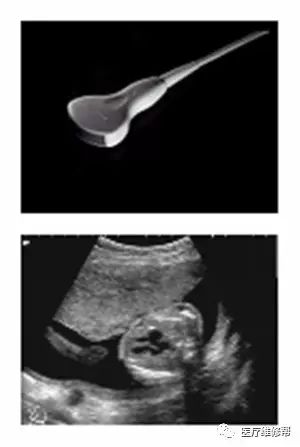

(二)一般常见的B超探头

1、凸阵探头3.5MHz 2、线阵探头3.5MHz 3、高频线阵7.5MHz 4、腔体探头6.5MHz 5、心脏探头3.2MHz 6、相控阵探头3.0MHz 7、三维探头3.5MHz